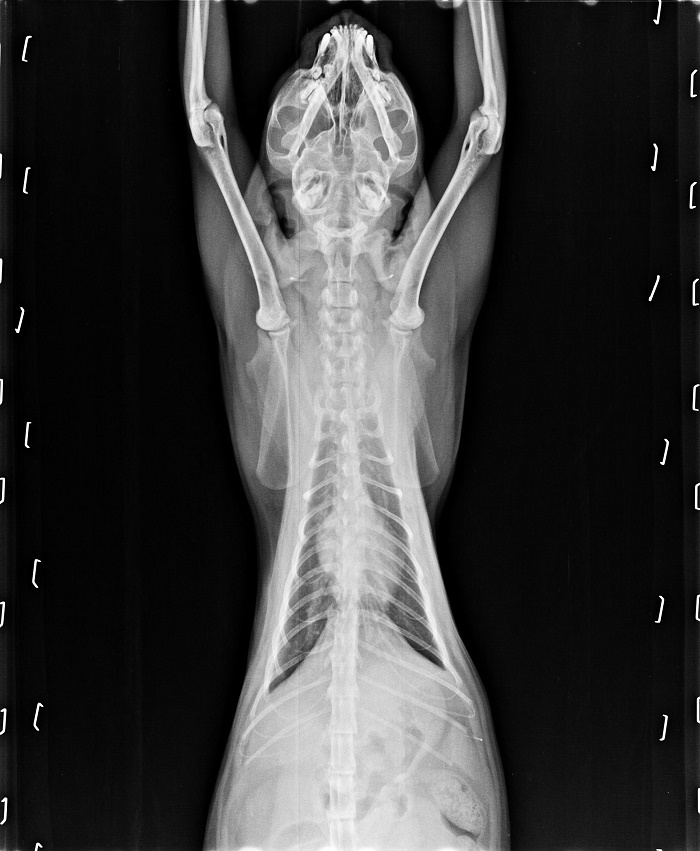

但可能之前在外流浪的食物不好,也沒有喝足夠的水,導致小葵口炎嚴重,牙齒一顆顆爛光,曾遭受重傷的她,個性緊張,無法刷牙,牙齦炎嚴重到口水一直分泌,她不小心吸入肺部,導致呼吸聲很大,怕拖下去越來越惡化,所以醫生在檢查過後,安排住院,先評估血檢、X光的情況,再給予洗牙、拔牙治療,拔了8顆爛牙後,小葵已出院,每天需噴一次口樂和拿賽可得,情況已獲得控制,只要半年洗牙一次就可以,她的住院費用,還需要大家的幫忙,讓這個小女孩的牙齒,可以保住,讓曾經飽受摧殘的她,能夠好好的吃一頓飯。